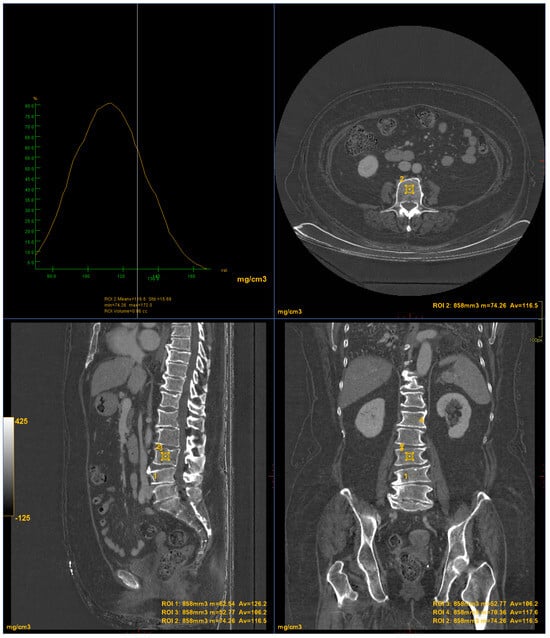

DXA scans were performed using a bone densitometer (Discovery A, HOLOGIC, Marlboroug, MA, USA) for the lumbar vertebrae (L1 to L4) and femoral neck (Figure 1 and Figure 2).

Figure 2. DXA measurements on the femoral neck (Regione: measurement region; Area: measurement area; BMC: Bone Mineral Content; BMD: Bone Mineral Density; PR: Reference peak; AM: Age Matched).

CT images were processed using AW3.2 software (GE Healthcare, Chicago, IL, USA) with a bone window and HAP–fat base material pairing, which highlights structures containing hydroxyapatite. Three-dimensional volume of interest (VOI) measurements were obtained at the lumbar vertebrae (Figure 3) and femoral neck (Figure 4), sampling the trabecular bone while excluding cortical bone regions.

Figure 4. DECT measurements on the femoral neck (ROI5: femoral neck volume measurement). The ROI volume was 858 mm3.